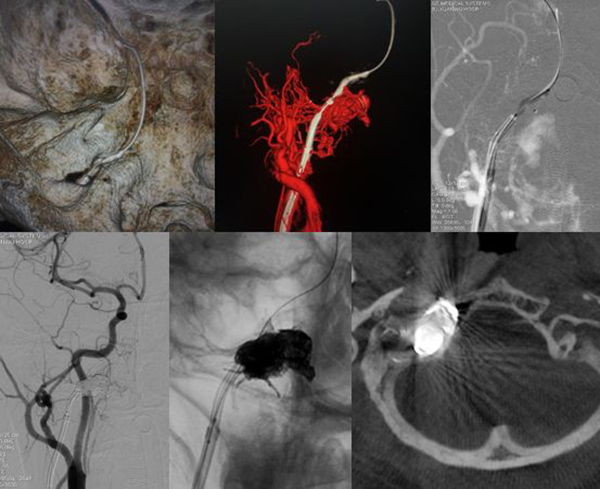

复合手术治疗大型动脉瘤并发表研究成果

领先开展颅内动脉瘤介入栓塞新技术

复合手术切除脑和脊髓血管畸形

硬脑膜动静脉瘘治愈性栓塞的引领者